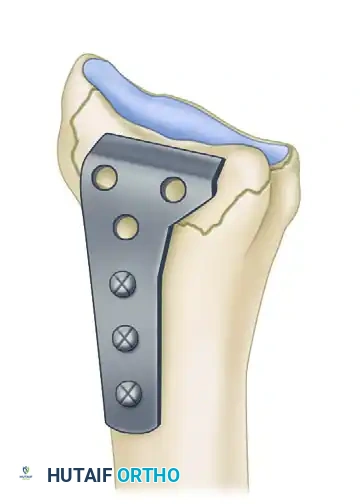

Image

The L-plate provides a volar buttress to the volar rim of the lunate facet, yet allows fixation to the subcutaneous radial side of the proximal fragment, minimizing tendon abrasion.